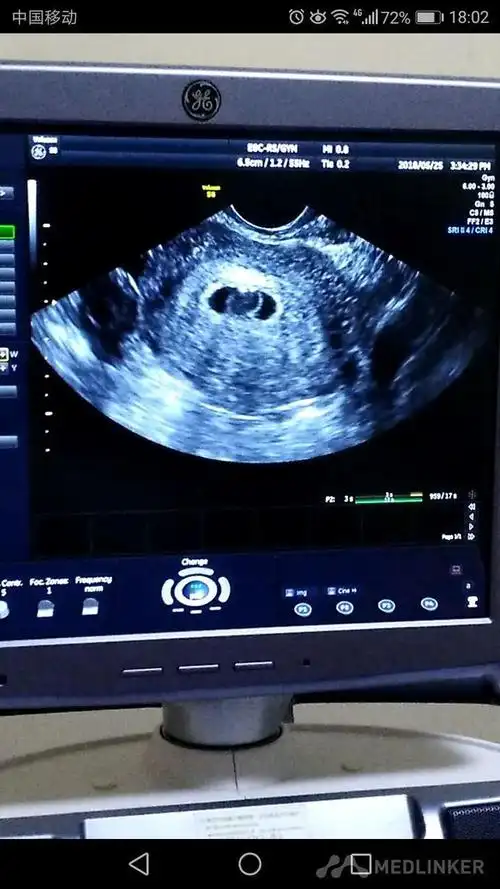

诊断 处理发病以来,未用药,二便正常,无腹痛随访 讨论停经43天,阴道不